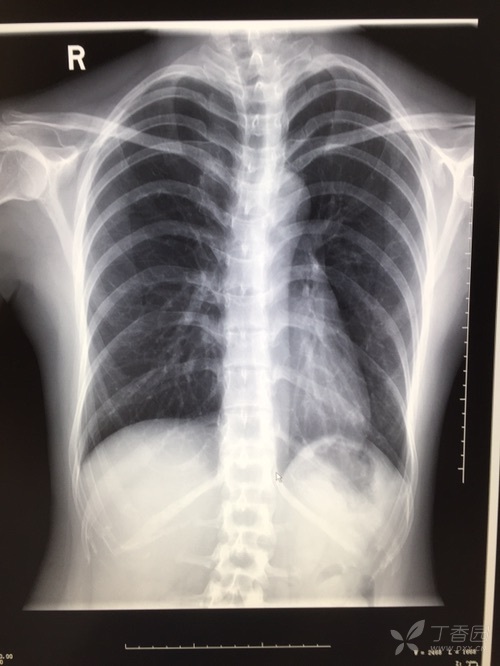

轨道征胸片

此次患者因咯血就诊,胸片显示双下肺(尤其是右肺)浸润影,伴多发环状

仔细观察胸片时也可能发现双轨征,提示支气管壁明显增厚.